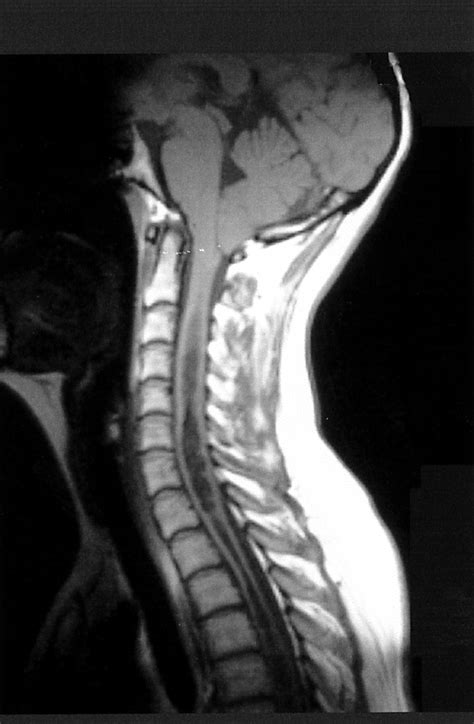

At its core, Chiari Type 2 involves the downward displacement of the cerebellar tonsils, the brainstem, and the fourth ventricle through the foramen magnum, which is the large opening at the base of the skull. This displacement creates a bottleneck effect that interferes with the normal flow of cerebrospinal fluid (CSF). Because this condition is developmental, it typically manifests in infants, as the structural abnormalities are present from birth.

MRI (Magnetic Resonance Imaging) Provides detailed images of the cerebellum, brainstem, and spinal cord to assess the degree of herniation.

1. Decompression Surgery: A neurosurgeon removes a small piece of bone at the back of the skull (and sometimes the top of the spinal canal) to create more space for the cerebellum and restore normal CSF flow.